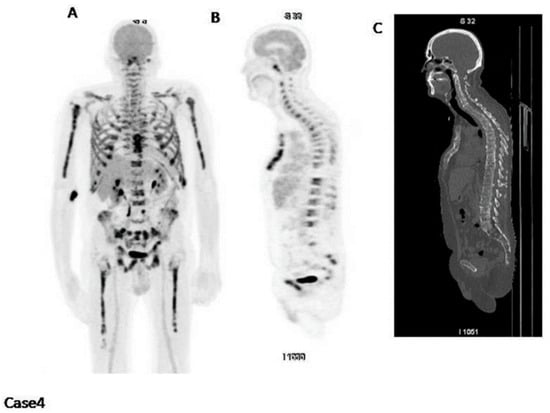

Figure 7.

(A) This image displays the whole-body Na[18F]F PET scan without the application of regions of interest (ROIs). (B) Active lesions including fractures throughout the whole-body Na[18F]F PET/CT scans were identified and segmented; PMID: 32929393, Figure 1, open access.

In a research conducted by Ak et al. [39], even though there were certain limitations to the ability of Na[18F]F PET to identify osteolytic lesions, this radiotracer managed to identify 135 bone lesions, encompassing rib fractures and other anomalies linked to degenerative alterations. Hence, the researchers concluded that Na[18F]F PET/CT might offer a complementary function in identifying fractures linked to myeloma [39]. In another study conducted by Sachpekidis et al., the Na[18F]F PET/CT scan revealed only 135 lesions indicative of MM, whereas the whole-body [18F]FDG PET/CT scan depicted a total of 343 focal lesions [40]. Nonetheless, Na[18F]F PET/CT revealed indications of degenerative processes associated with trauma [40].

The presence of fluoride in Na[18F]F serves as a direct marker of osteoblastic activity, as it is specifically incorporated into newly formed bone mineral sites that are exposed [41]. Consequently, Na[18F]F PET can be utilized to evaluate bone turnover in different medical conditions. Zirakchian Zadeh et al. investigated the effects of high-dose therapy (HDT) and conventional-dose chemotherapy on the uptake of Na[18F]F in myeloma patients [42]. In total, 19 patients with MM who received HDT and an additional 11 MM patients who received chemotherapy at standard doses were included in the study (Figure 8) [42]. Following HDT, myeloma patients exhibited a noticeable decrease in Na[18F]F uptake in various areas, including the overall skeleton, pelvis, entire femoral neck, and lateral femoral neck. Conversely, in the non-HDT group, no significant alterations were observed (Figure 8) [42]. As a result, the authors inferred that Na[18F]F holds potential for evaluating bone loss in myeloma patients after HDT [42].

Figure 8.

The images on the left depict a semi-automated CT-based segmentation used to assess bone turnover in the entire bone and pelvis of multiple myeloma patients before and after treatment (a,b). Regions of interest were also delineated to evaluate changes in Na[18F]F uptake in the femoral neck of these patients (c). Images obtained from comparison of Na[18F]F uptake in the whole bone, pelvis, and femoral neck of multiple myeloma patients before and after high-dose therapy and conventional-dose chemotherapy, Zirakchian Zadeh et al., EJNMMI, Figures 2 and 5, obtained with permission; reference [42] in this review article.